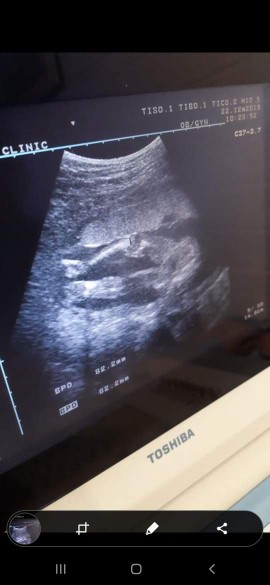

วันนี้ไปตามหมอนัดมาค่ะ ได้รู้เพศลูกแล้ว ดีใจมากค่ะ คลอด พค.ค่ะ บ้านไหนได้ลูกผู้ชายบ้างคะ ?❣️

เห็นจู๋ ชัดมากค่ะแม่ ยินดีด้วยนะคะ